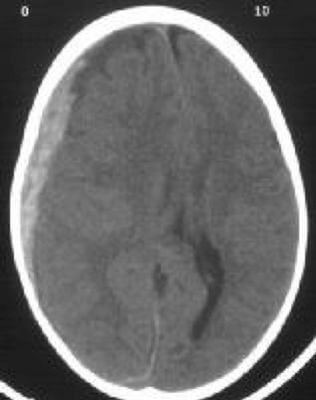

Поширені аномалії, що виявляються на КТ

За допомогою КТ можна виявити цілий ряд патологій, включаючи пухлини, кісти та інші утворення. КТ-сканування також корисне для виявлення переломів кісток, захворювань легенів і згустків крові.

Однією з найпоширеніших патологій, що виявляються на КТ, є вузлики в легенях. Ці невеликі утворення можуть бути доброякісними або раковими, і для визначення їхньої природи може знадобитися подальше обстеження.